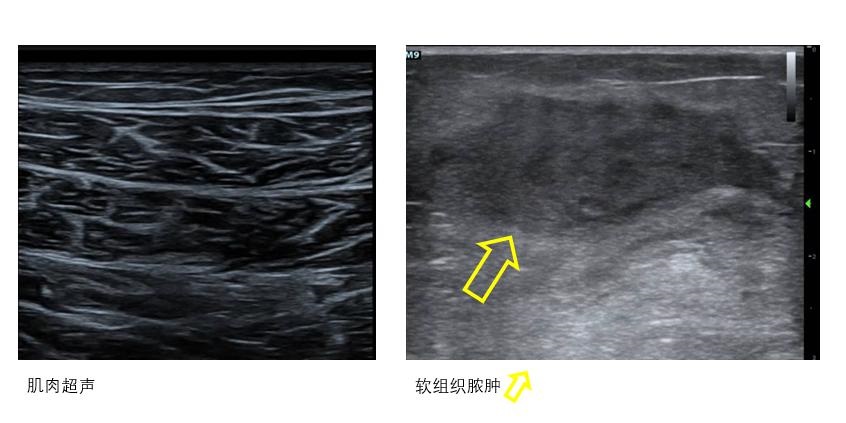

在实施ECMO过程中对包括膈肌和骨骼肌在内的肌肉活动度和肌肉密度、厚度进行超声监测可以协助营养治疗和康复训练等[22](图 24)。

|

| 图 24 肌肉和软组织超声 |

出血是ECMO患者常见的并发症,床旁超声可通过直接或间接超声证据协助判断出血部位、血肿范围、对周围组织器官压迫情况等(图 25)。明确出血部位和出血量可为抗凝强度调整提供参考,此外,超声还可以协助积血定位和穿刺引流。

| 图 25 出血 |